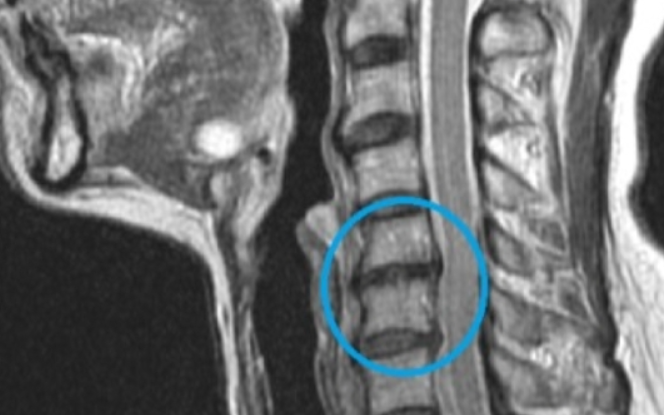

목디스크를 진단하려면 전문의가 종종 엑스레이, MRI, CT 스캔 등을 사용하여 목 디스크의 위치와 심각도를 파악합니

다. 치료법은 디스크가 심하게 손상되었는지, 디스크가 충분히 유지되어 있는지, 그리고 신경이 손상되었는지 여부에 따라

치료방법을 선택하시면 될 것 같습니다.